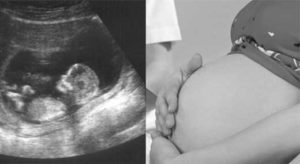

Часто этот диагноз ставят на основании УЗИ органов малого таза. Нормальными размерами матки считаются: длина 7-8 см, ширина 4-5 см, толщина миометрия 2-3 см.

Маленькая матка (фото с монитора аппарата УЗИ):

УЗИ диагностика основана на визуальном измерении размеров матки на мониторе аппарата. Однако метод не учитывает особенностей нормального развития.

У женщин с астеническим телосложением, возможно, размеры матки будут меньше статистической нормы, однако никаких проблем женской половой сферы у них нет.

Размер определяется на ультразвуковом исследовании и бывает: продольный 7—8 см, поперечный 4—5 см. Большое значение для того чтобы забеременеть и выносить ребенка имеет толщина мышечного слоя, она должна быть в пределах 2—3 см.